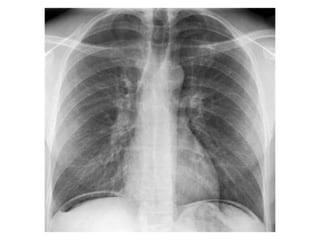

pleura

• The retracted visceral pleura is seen (blue arrow)

which indicates that there is a pneumothorax.

• There is a horizontal line visible (yellow arrow).

Normally there are no straight lines in the human

body unless when there is an air-fluid level.

This means that there is a hydro-pneumothorax.

• When a pneumothorax is small, this air-fluid level

can be the only key to the diagnosis of a

pneumothorax.